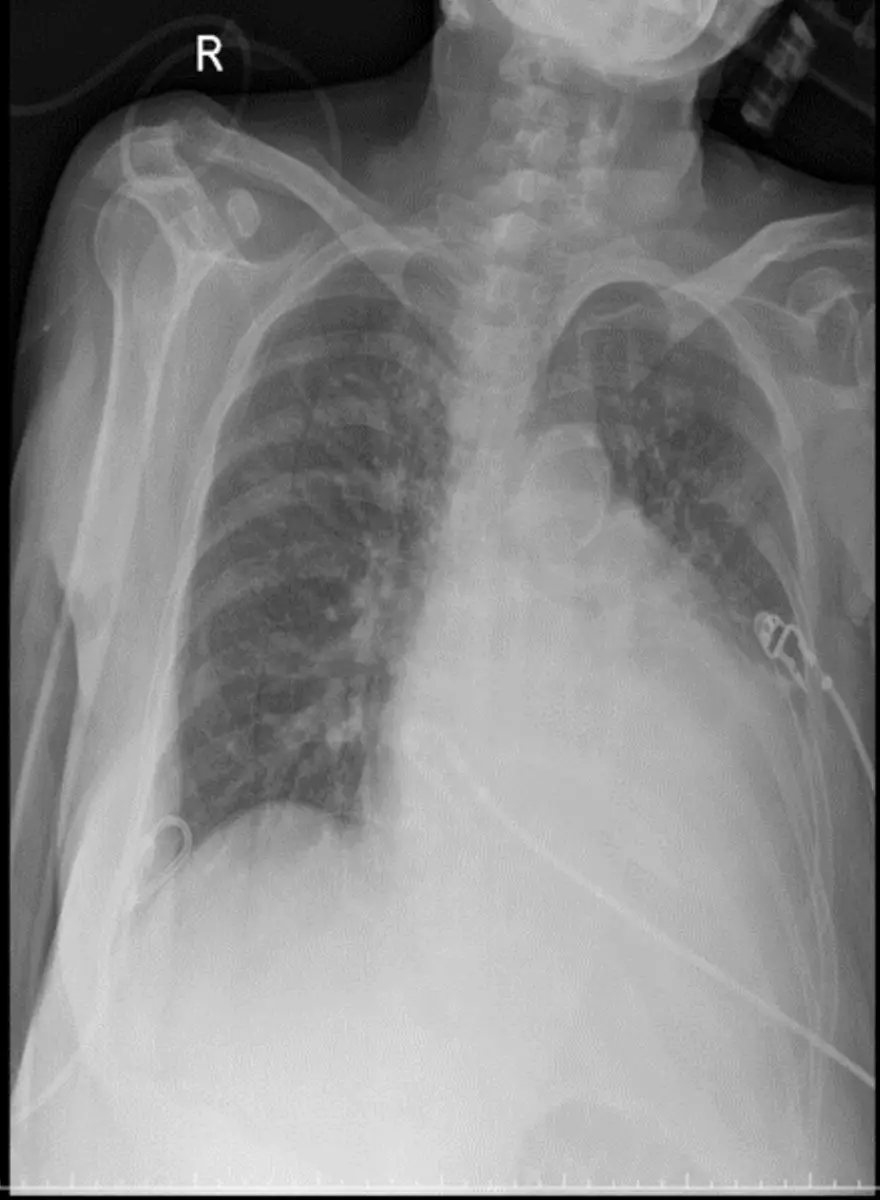

胸部 X 光:

- 心影增大,雙肺下葉廣泛性浸潤影、胸水徵象(肺紋理增粗、胸膜輕度積液),符合肺水腫。

- 硬體導管影(中央靜脈導管或 Swan–Ganz 導管)置放於右肺附近,顯示已經監測或支援血流動力。